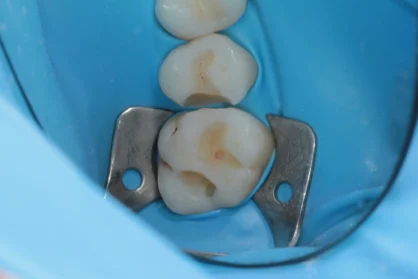

Приклади робіт лікаря-стоматолога

Естетична реставрація. До / після